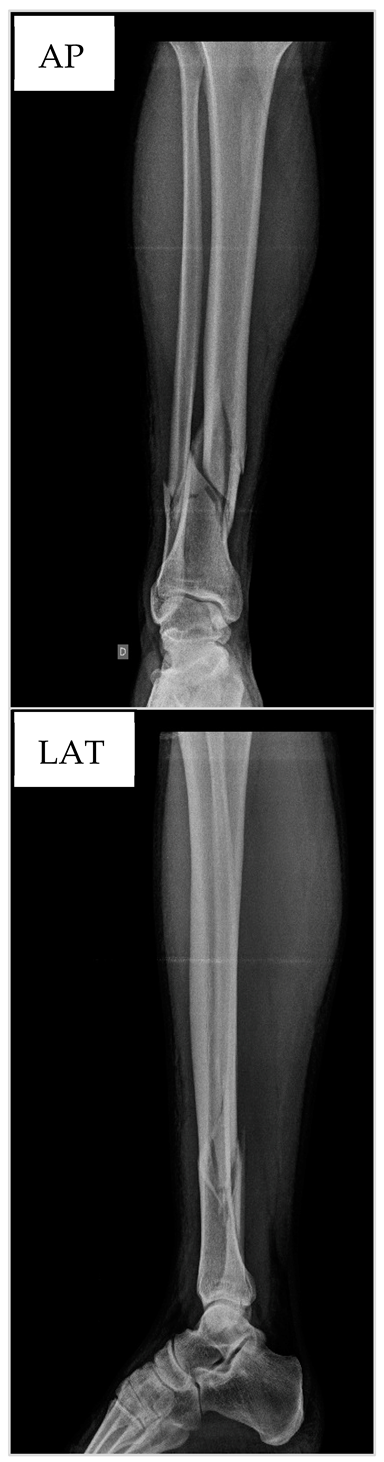

3.1. Patient nº1